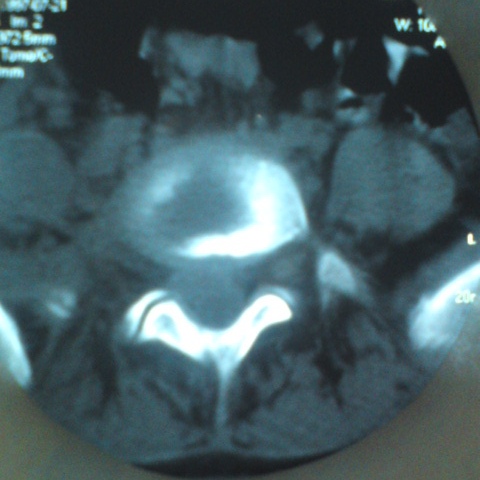

标题: CT27836:女 ,13岁,腰痛数月,加重一月,检查下腰部明显压 [打印本页]

标题: CT27836:女 ,13岁,腰痛数月,加重一月,检查下腰部明显压

考虑腰椎结核,建议做椎体扫描。

考虑腰4椎体结核伴右侧椎旁及椎管右侧硬脊膜外脓肿形成。

考虑腰椎结核伴右侧椎旁及椎管右侧硬脊膜外寒性脓肿形成;建议必要时行mri检查。